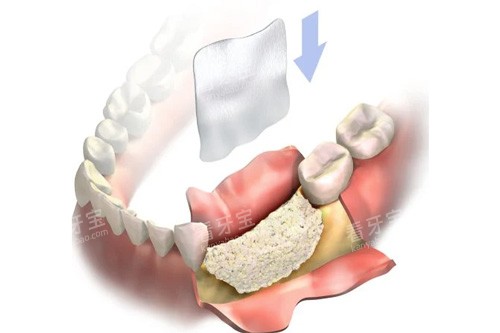

绮云的医生团队,简直像达州的“口腔天团”!张晓云院长,30年种植经验,完成超5000例手术,擅长前牙美学种植、ALL-ON-4全口种植,连高难度的上颌窦提升术都不在话下。患者王阿姨说:“张医生种牙,比绣花还精细,我种完当天就能吃面条,现在啃排骨都没问题!”

北平的医生团队,主打“灵活”和“小创口”!黄北平院长,20年临床经验,擅长复杂种植和骨增量手术,个人种植实例超3000例。患者刘先生说:“黄医生给我种牙,用智能化导板设计,精度高得吓人,创口比芝麻还小,修养得特别快!”

绮云的技术,简直像达州的“口腔百科全书”!种植牙方面,从小创口即刻种植到ALL-ON-4全口种植,从韩国进口种植体到瑞典诺贝尔种植体,技术全覆盖。矫正方面,钢丝、陶瓷、隐形、舌侧矫正样样行,还能做儿童早期矫治。患者周女士说:“我在绮云矫正牙齿,医生用数智化口扫仪,5分钟就让我看到矫正后的结果,太神奇了!”

北平的技术,主打“小创口”和“智能化”!种植牙方面,采用韩国奥齿泰种植系统,小创口即刻种植,当天拔牙当天种,适合前牙区即刻修复。矫正方面,用DSD智能化微笑设计,通过3D模拟提前预览结果,正畸方案设计费800-1500元起。患者吴先生说:“我在北平矫正牙齿,医生用显微根管治疗,保留了更多健康牙体组织,现在我的牙齿比以前结实多了!”